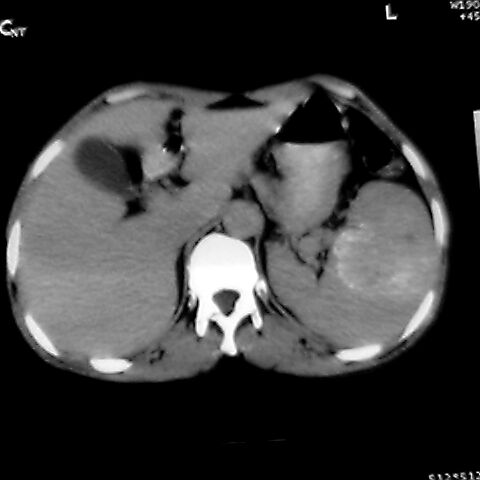

女 48岁 食道癌术前体检发现脾占位。

1肝右下叶小囊肿2右肾上极囊肿或错构瘤3脾脏不典型血管瘤可能性大.

脾脏低密度灶伴钙化,增强化明显,中心见液化坏死灶,强化延时明显。考虑血管瘤。转移瘤待排。

1,脾血管瘤。2,右肝,右肾小囊肿。